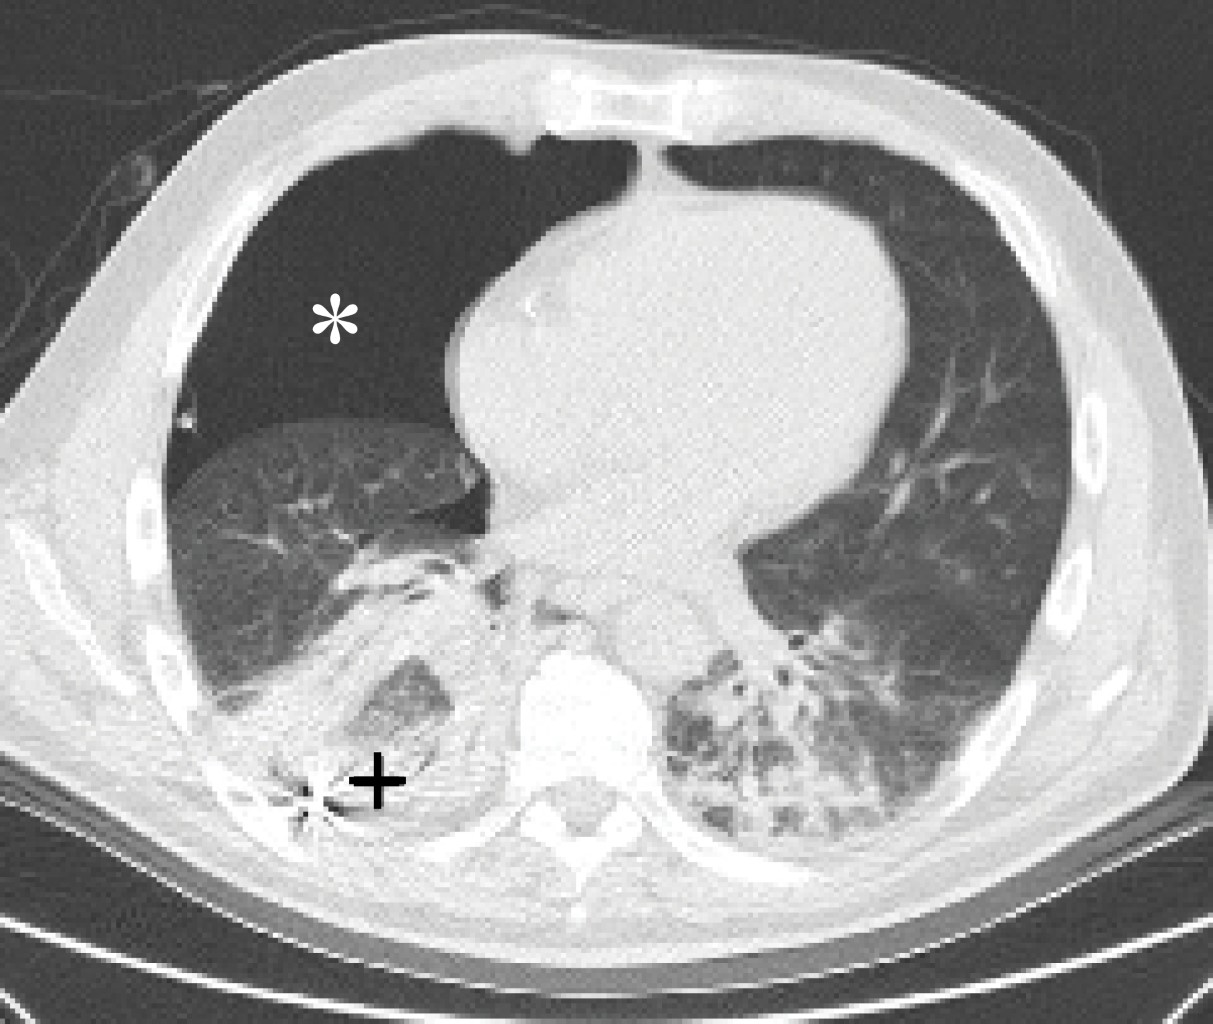

Hombre de 54 años de edad que presentó paro cardiorrespiratorio secundario a infarto de miocardio con angiografía coronaria de rescate exitosa. El paciente cursó con choque cardiogénico, lesión renal aguda KDIGO (Kidney Disease Improving Global Outcomes) 1 y fue extubado por mejoría de las disfunciones orgánicas a los siete días de su ingreso. Debido a la presencia de delirio postextubación y disfagia a sólidos que dificultó la administración de nutrición enteral y el tratamiento antiisquémico, se decidió la colocación de una sonda nasogástrica con técnica ciega, sin éxito después de seis intentos, por lo que se optó por una sonda nasoyeyunal de poliuretano con guía metálica y punta de tungsteno; sin embargo, luego de su colocación el paciente presentó hipoxemia y choque circulatorio que ameritó reintubación orotraqueal y vasopresores. Se realizó ultrasonido pulmonar y radiografía portátil de tórax, con lo que se evidenciaron signos ultrasonográficos de neumotórax y la punta metálica de la sonda nasoyeyunal fuera del tubo digestivo (Figura 1). Se confirmó mediante tomografía la perforación bronquial de la punta metálica de la sonda enteral, así como su localización en el espacio pleural y la expansión del neumotórax (Figura 2). El Departamento de Cardiotórax retiró la sonda nasoyeyunal y colocó una sonda endopleural a las dos horas del evento, lo que permitió la expansión pulmonar (Figura 3). Mientras que la sonda enteral postpilórica fue colocada a través de endoscopia por el Departamento de Otorrinolaringología a las 24 horas, la sonda endopleural fue retirada a los seis días de su instalación.

Figura 2